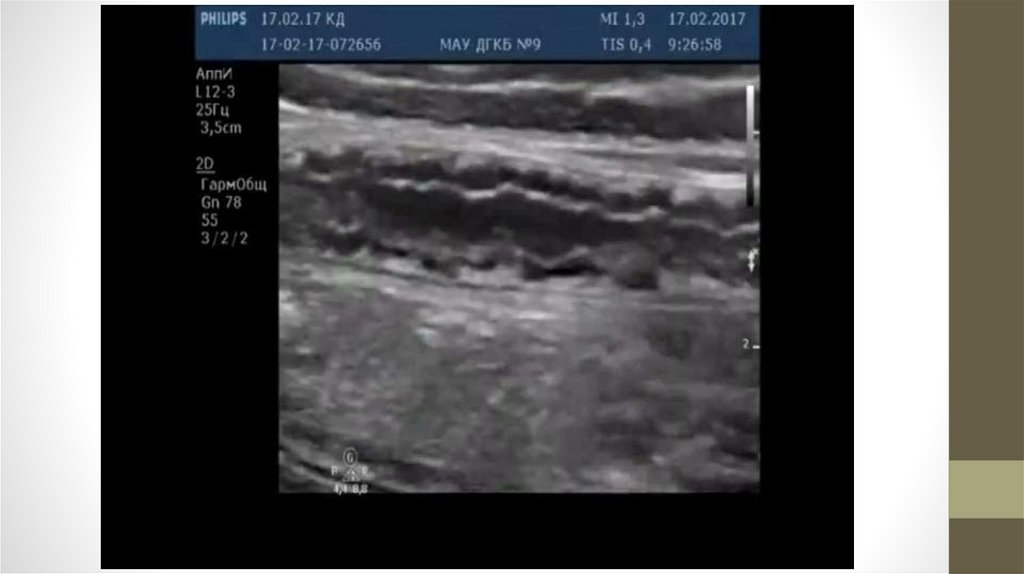

Изменения в сосудах

Атеросклеротические бляшки – наложения на внутренней стенке сосуда (артерии)

холестерина и кальция.

При увеличении бляшки возникает нарушение кровотока по сосуду вплоть до полного

прекращения.

Обычно возникают в пожилом возрасте, но нередко обнаруживаются и у молодых людей.